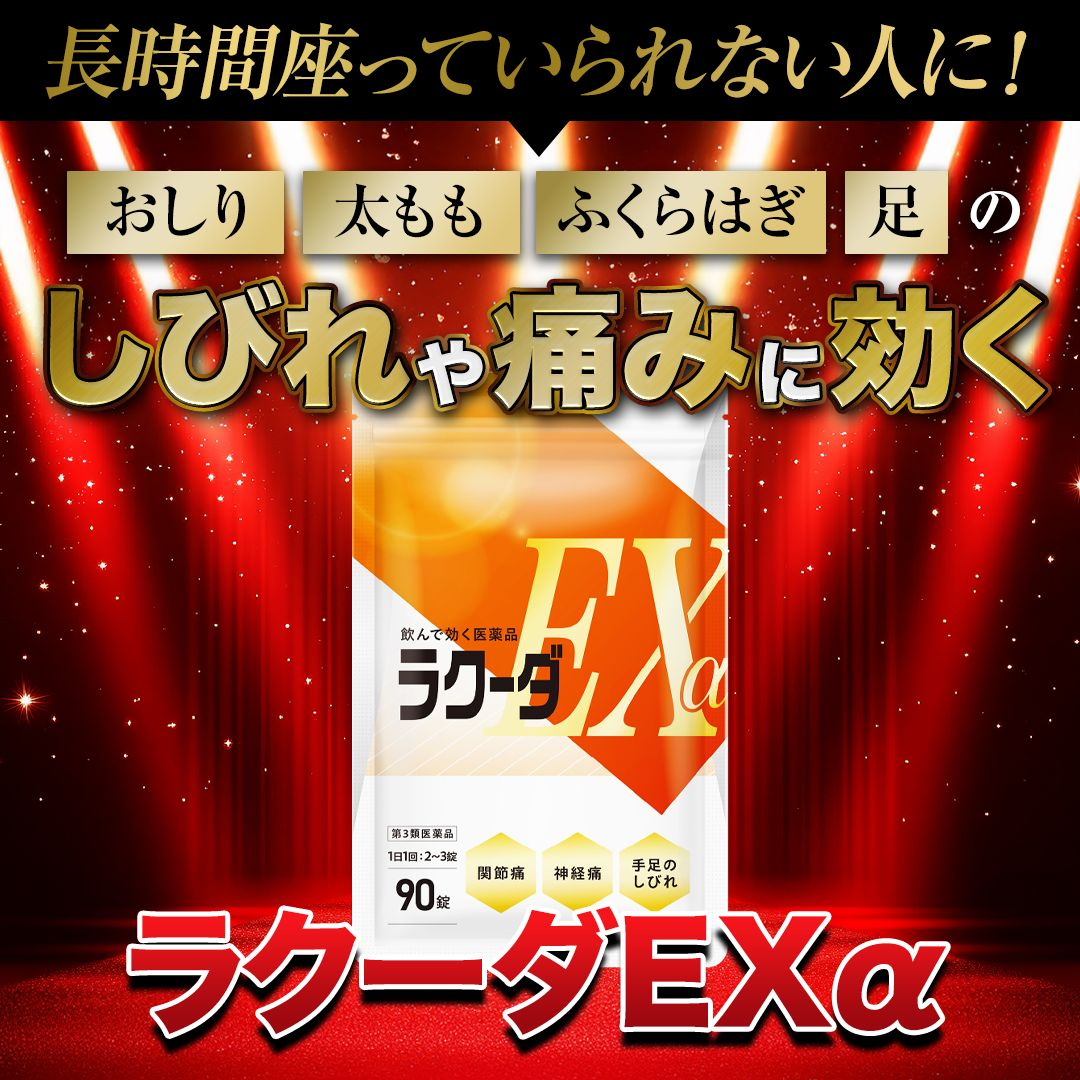

- 足全体がビリビリしびれて痛い

- おしりから太もも〜ふくらはぎにかけてズーンと鈍痛がある

- おしりの奥がズキズキと刺すように痛い

- 立ち上がる瞬間、電気が走るようにビリっと痛む

これらは坐骨神経痛と呼ばれる症状ですが、

「ラクーダEXα」

この薬を知らない人もいるかもしれませんが、

なんとこのラクーダEXα、

大正6年創業の老舗医薬品メーカー

が開発した信頼の医薬品!

サプリや機能性表示食品ではなく

「医薬品」に分類されるため

効果が国に認められているんです!

だから今、

TVや新聞でも大きく取り上げられていて、

「坐骨神経痛の根本原因にはコレ!」

「座っていられない人の救世主!」

と口コミで話題!

ついに累計販売数2000万袋を突破!

いま最も注目されている医薬品なんです!